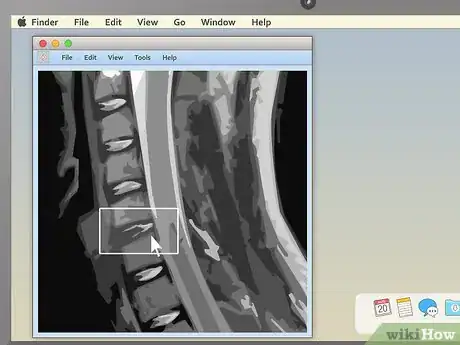

5Drag the section-cut line to view new parts of the study. Dragging the section-cut line to a different part of the image allows you to "move around" your MRI images. The image should change your view to the new area automatically.

- For example, if you're viewing a sagittal image of your spine along with a cross section of one of your vertebrae, moving the section-cut line may allow you to cycle up and down through the various vertebrae above and below it. This can be useful for locating problems like herniated discs.

1Look for non-symmetrical patches. By and large, the body is very symmetrical. If, in your MRI, you notice a patch of lightness or darkness on one side of your body that does not match what's on the other side, this can be cause for concern. Similarly, for parts of the body that have many similar features repeated multiple times, a difference in one of the features can be a sign that something is amiss.

- A good example of the second case is for spinal disc herniations.[6] The spine is made up of many different bone vertebrae stacked on top of each other. Between every two vertebrae is a fluid-filled disc. When you get a herniated disc, one of these discs breaks and the fluid leaks out, causing pain as it presses against the nerves in your spine. You'll be able to see this on a spinal MRI — there will be a long line of "normal" vertebrae and discs, with one noticeably bulging out.